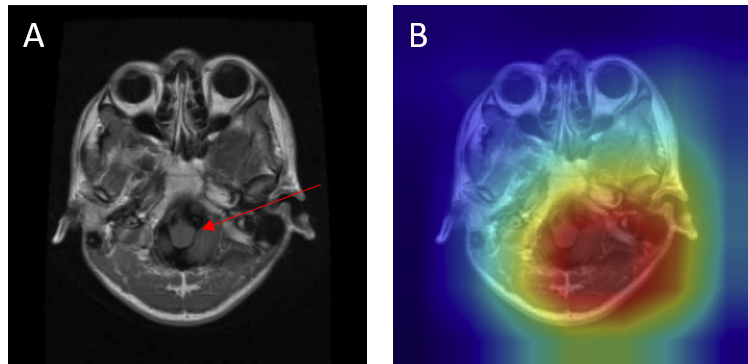

Grad-CAM visualizations of correctly classified cases confirm that the model focuses on regions consistent with radiological expectations. In these overlays, warmer colors (red and orange) highlight the areas where the network places the greatest emphasis during prediction, while cooler colors (blue) correspond to regions with minimal contribution. This distinction allows direct inspection of whether the model bases its decision on clinically relevant cues.

For gliomas, the heatmaps align with intra-axial lesions exhibiting infiltrative margins (Figure 8). Meningiomas are accurately identified at dural or peripheral attachment sites, consistent with their extra-axial presentation (Figure 9). Pituitary adenomas are localized to the sella turcica with concentrated red activation at the lesion boundaries (Figure 10). Finally, in no tumor cases, the activation maps remain diffuse or midline-focused without strong hotspots, consistent with normal anatomy (Figure 11). The correspondence between the model's attention and radiological landmarks indicates that the network is learning meaningful diagnostic features rather than relying on spurious correlations.

Figure 9: Meningioma — original (A) vs. Grad-CAM (B), correct model prediction.

Meningioma Correct